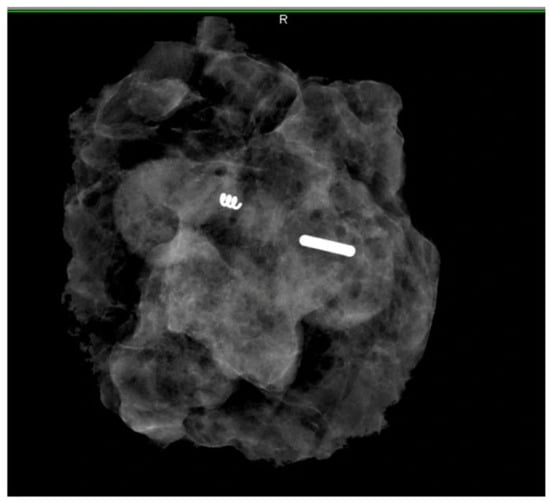

3.1. Literature Search Results

3.2. Subsection

- Successful localisation rate: 97.6% (560/574) [95% confidence interval (CI), 0.97–0.98].

- Retrieval rate: 99.8% (573/574).

- Concordance rate between SLNBs and MLNBs: 60.0% (289/481) [95% CI, 0.56–0.64]. Subgroup analysis of studies reporting the pathological status of MLNBs and SLNBs separately revealed a FNR of 5.2% for MLNBs and 18.8% for SLNBs. Chi squared equaled 18.398 with 1 degree of freedom. The two-tailed p value was less than 0.0001.

- pCR was observed in 44% of cases (248/564) [95% CI, 0.35–0.45], with no reported migration or procedure-specific complications.

- The successful deployment rate was 100%, but one patient required repeat deployment due to seed misplacement during ultrasound-guided localization [18].

- Localisation was compromised in one patient due to the inability to visualise the clip by ultrasound, which led to subjecting the patient to ALND [18].

- The pooled average number of lymph nodes retrieved during the TAD procedure was 2 (range: 1–11).

- The pooled average interval duration from magnetic seed deployment to surgery was 75 days (range: 0–272 days).

| Study | Citation | Number of Patients Pre- or Post-NST | Mean Age in Years | pCR (%) | Retrieval Rate | Localization Success Rate | Migration Rate | Mean Implantation Duration (Days) | Median Number of Nodes Harvested | SLNB–MLNB Concordance Rate | FN MLNB | FN SLNB |

|---|---|---|---|---|---|---|---|---|---|---|---|---|

| Zatecky et al. (2023) | [13] | 142 | 51 (26–82) | 58/142 (40.8%) | 142/142 (100%) | 141/142 (99.3%) | 0 | 146.5 (101–272) | 2 (0–7) | 94/130 (72.3%) | 6/84 | 18/84 |

| Munck et al. (2023) | [18] | 135 | 49.4 (26–80) | 84/135 (62.2%) | 135/135 (100%) | 128/135 (94.8%) | 4/135 | 0 | 3.2 (1–10) | 35/128 (27.3%) | 0/51 | No data |

| Simons et al. (2022) | [19] | 227 | 52 (22–77) | 70/223 (31.4%) | 227/227 (100%) | 223/227 (98.2%) | 0 | 2 (1–8) | 134/188 (71.3%) | 10/155 | 22/129 | |

| Beniey et al. (2021) | [20] | 35 | 49 (29–76) | 17/34 (50%) | 34/35 (97.1%) | 34/35 (97.1%) | 1/35 | 0 (day of surgery) | - | - | - | - |

| Diego et al. (2016) | [21] | 30 | 55 (30–71) | 19/30 (63.3%) | 30/30 (100%) | 29/30 (96.7%) | 0 | 4 (1–11) | 22/30 (73.3%) | 0/11 | - | |

| Caudle et al. (2015) | [22] | 5 | 55 (35–69) | 5/5 (100%) | 5/5 100% | 0 | 5 (0–5) | 2.4 (1–6) | 4/5 (80%) | - | - | |

| Total | 574 | 51.9 (22–82) | 248/564 (44%) | 573/574 (99.8%) | 560/574 (97.6%) | 5/170 (2.9%) | 75.8 (0–272) | 2 (0–11) | 289/481 (60.0%) | 16/301 (5.3%) | 40/213 (18.8%) |